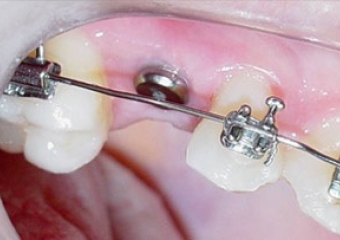

Imagem Inicial - Implante Instalado